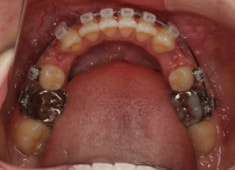

治療法:フルパッシブブラケット:T21

治療後(2年9ヶ月後)